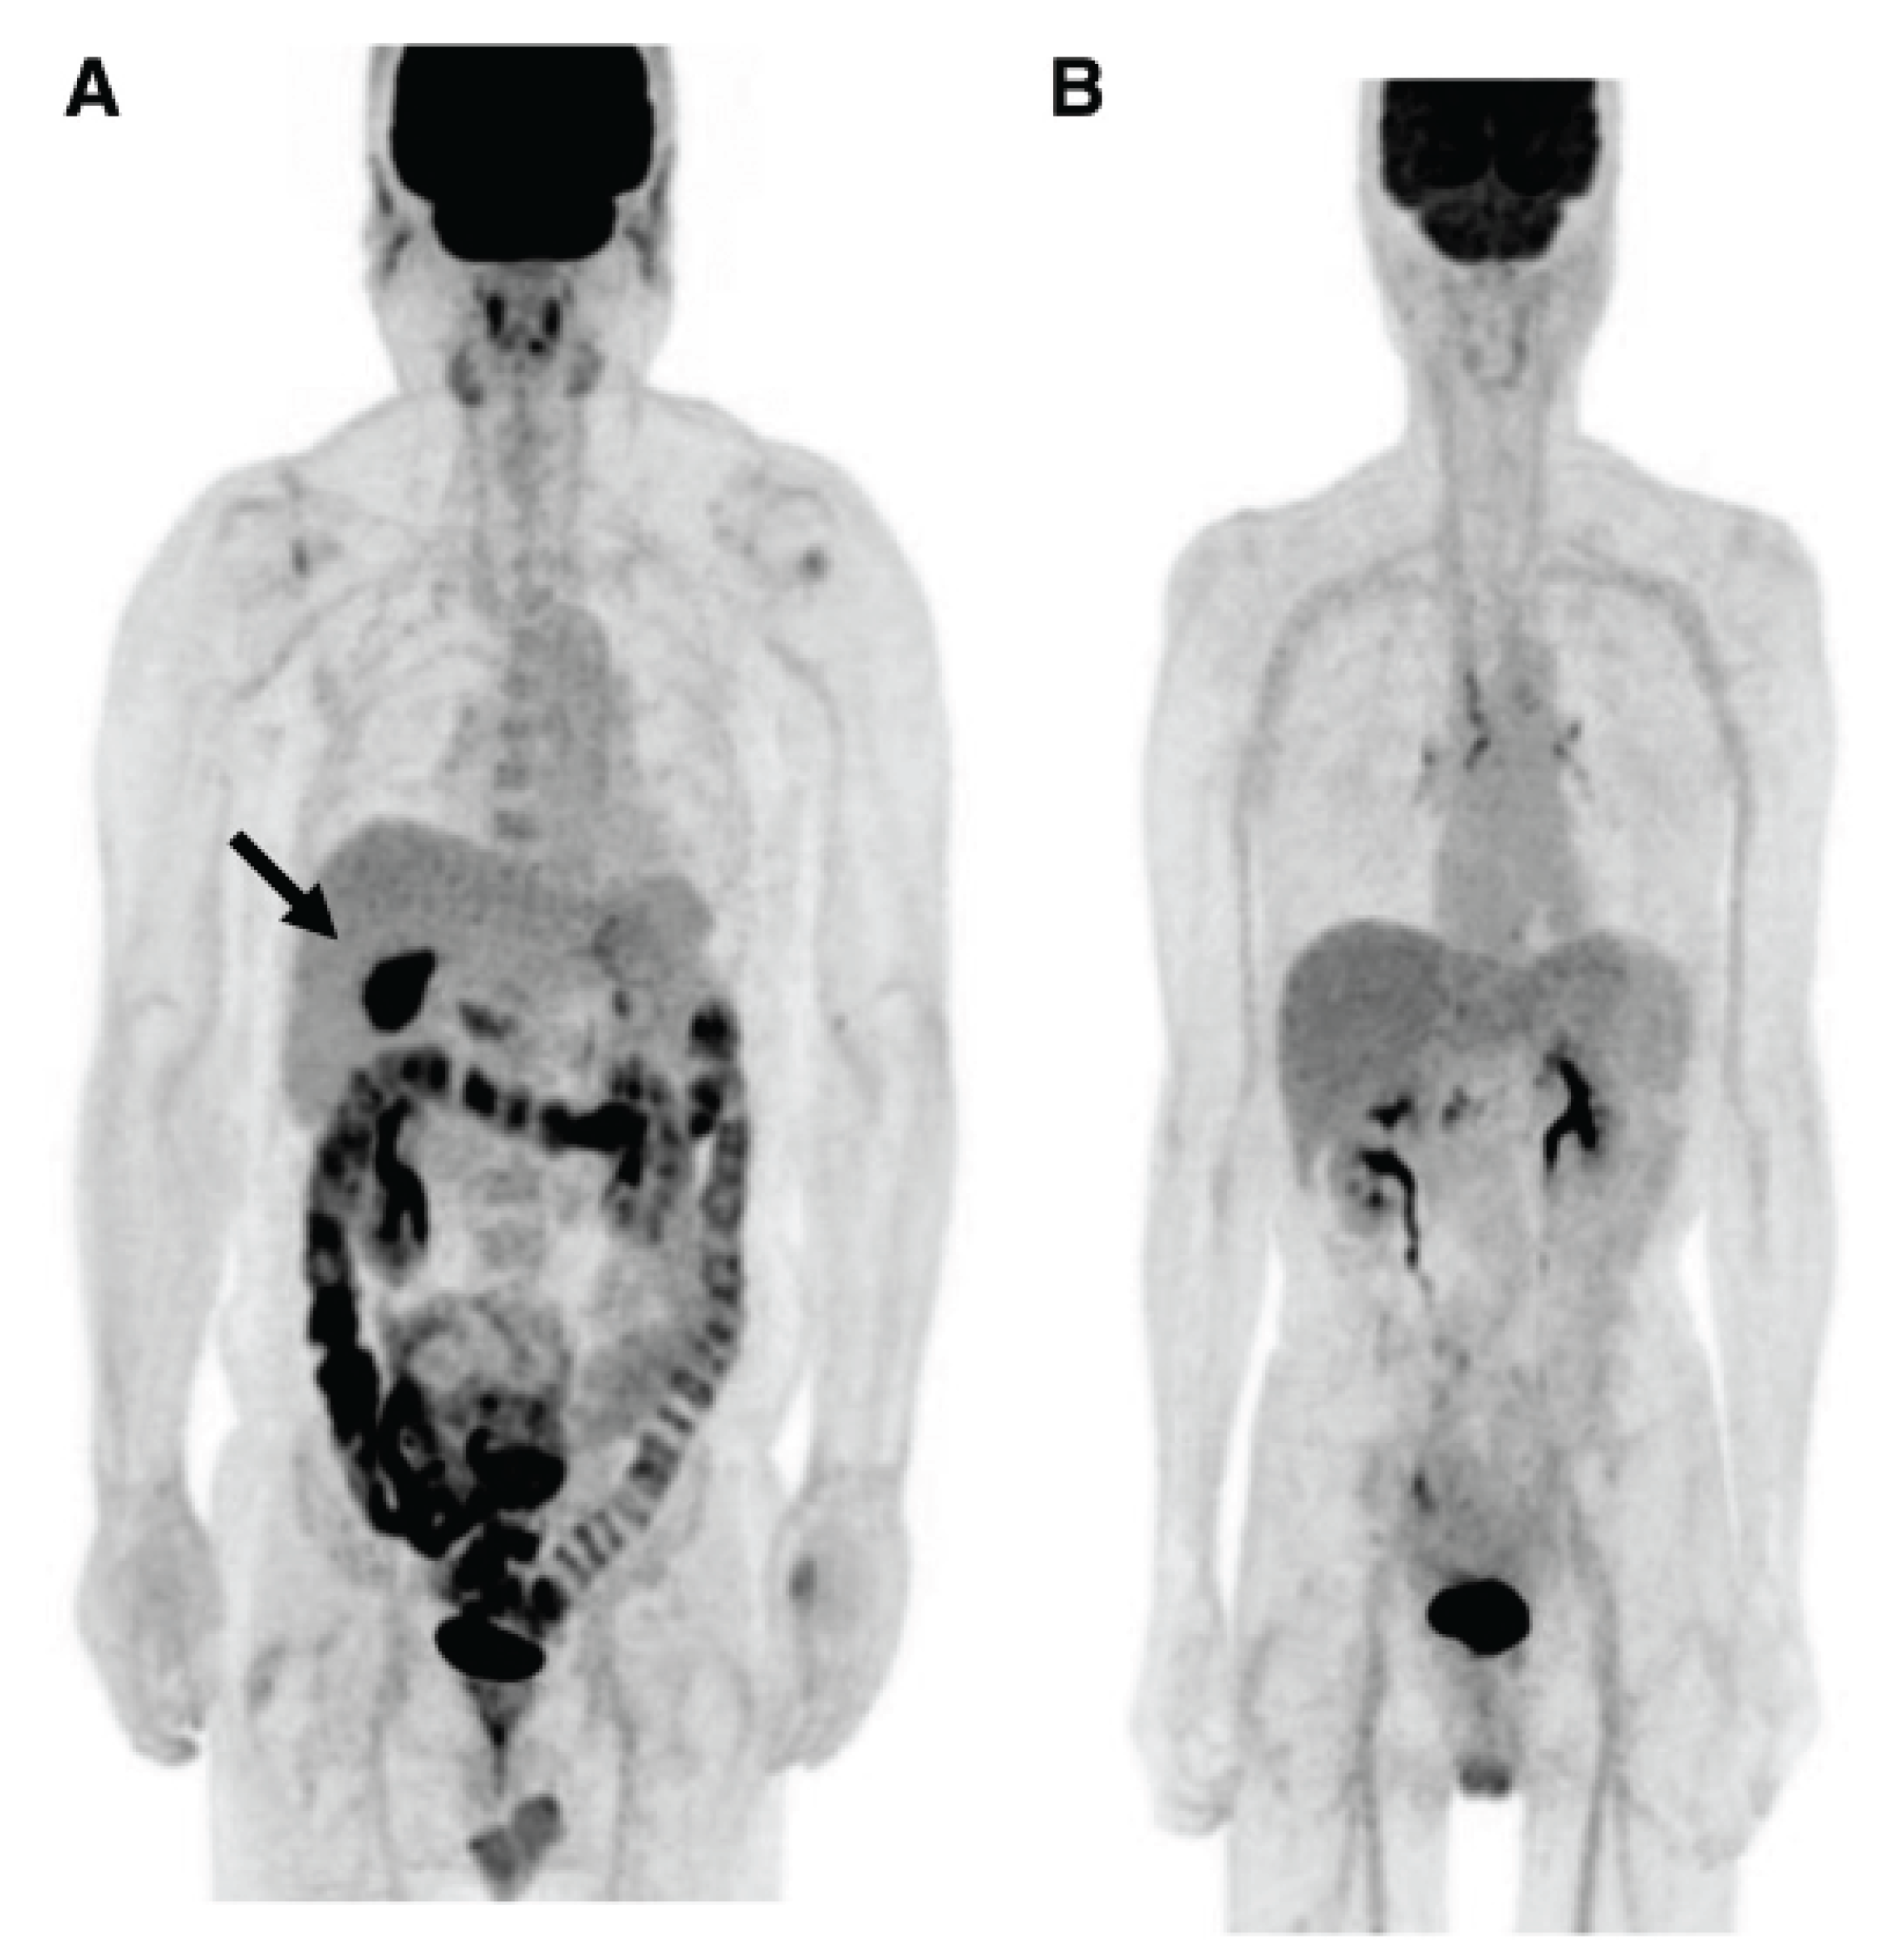

In a retrospective analysis, Kim and coworkers [187] described an accumulation of injected F18-FDG in the lumen of patients suffering of non-inflammatory diarrhea or constipation, and, for the first time intravenously injected, radioactive glucose in the stool. Gontier and colleagues [188] retrospectively studied the localization of F18-FDG injected in diabetics type 2 and found a significant increase of the radioactively-labelled glucose in the wall, but also in the lumen of the small bowel and of the colon in patients treated with metformin compared to that of non-metformin treated diabetics, which was not different from that of non-diabetics controls [188]. The authors stated that „the digestive tract is the only tissue responsible for a large glucose utilization enhancement“.

Morita and coworkers [189] by using positron emission tomography (PET)-MRI, recently found that the maximum standardized uptake value (SUVmax) of F18-FDG in the intestine (jejunum, ileum and right or left hemicolon) of metformin- treated diabetics was higher than that of the control group. More importantly, the study permitted to differentiate the SUVmax of the intestinal wall from that of the intestinal lumen. The SUVmax of the intraluminal space in metformin-treated diabetics was greater than that of controls (Figure 2). On the contrary the SUVmax of the intestinal wall was similar in both groups [189]. A temporarily increased accumulation of the injected tracer seems to be observed (Figure 3) also in the liver of metformin-treated diabetics up to 48 hours after interruption of the oral uptake of the drug [189,190,191] suggesting a persisting uptake of the radioactive glucose mediated by circulating insulin as consequence of the ”metabolic starvation”(?) induced by the biguanide.

Figure 2. PET-images taken 60 minutes after intravenous administration of F18-FDG in a diabetic patient treated with metformin (A) and in a control patient(B). In A radioactivity has accumulated in the last portion of the ileum and in the colon (right hemicolon stronger than left hemicolon). The indication for the study was gall bladder cancer as confirmed by the accumulation of the tracer in the gallbladder(arrow). From Morita Y et al. [189].